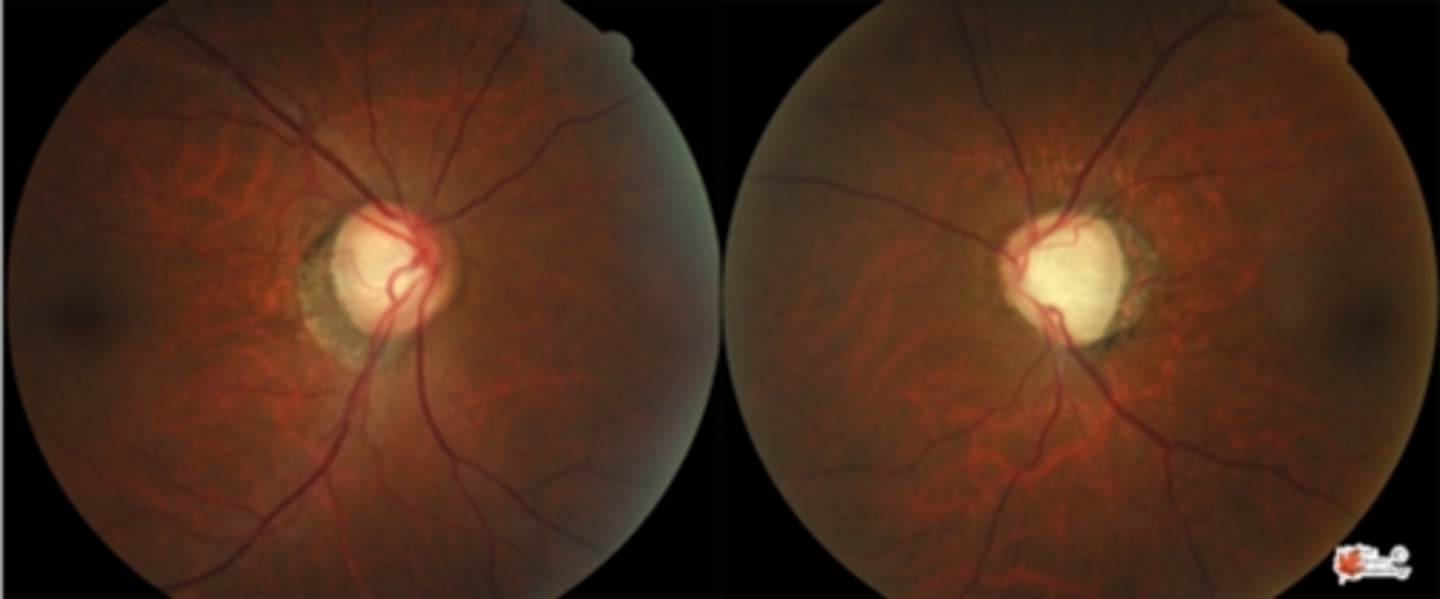

What cause of ascending optic atrophy is shown here?

AAION